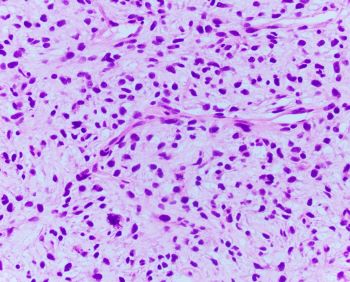

55 YOM presented with thigh mass. A biopsy was performed and showed the following lesion illustrated in the images. FISH analysis using a dual-color MDM2/CEN12 probe [Red=MDM2; Green=CEN12] was performed.

Histologically, dedifferentiated areas can be of high or low grade including area that resembles undifferentiated pleomorphic sarcoma, with pleomorphic spindle, polygonal, and multinucleated cells or with marked inflammation, or an area resembling inflammatory myofibroblastic tumor. Occasionally, the dedifferentiated component may resemble myxoid soft tissue neoplasm exhibiting myxoid stroma and delicate fibrovascular network entering the differential diagnosis with myxoid liposarcoma, myxofibrosarcoma, and low-grade fibromyxoid sarcoma. If present, the well-differentiated (lipogenic) component in dedifferentiated liposarcoma is mostly discrete showing an abrupt transition from the dedifferentiation component, but the two components can be intermingled in a mosaic pattern. Nonetheless, in small biopsies, only one component may predominate.